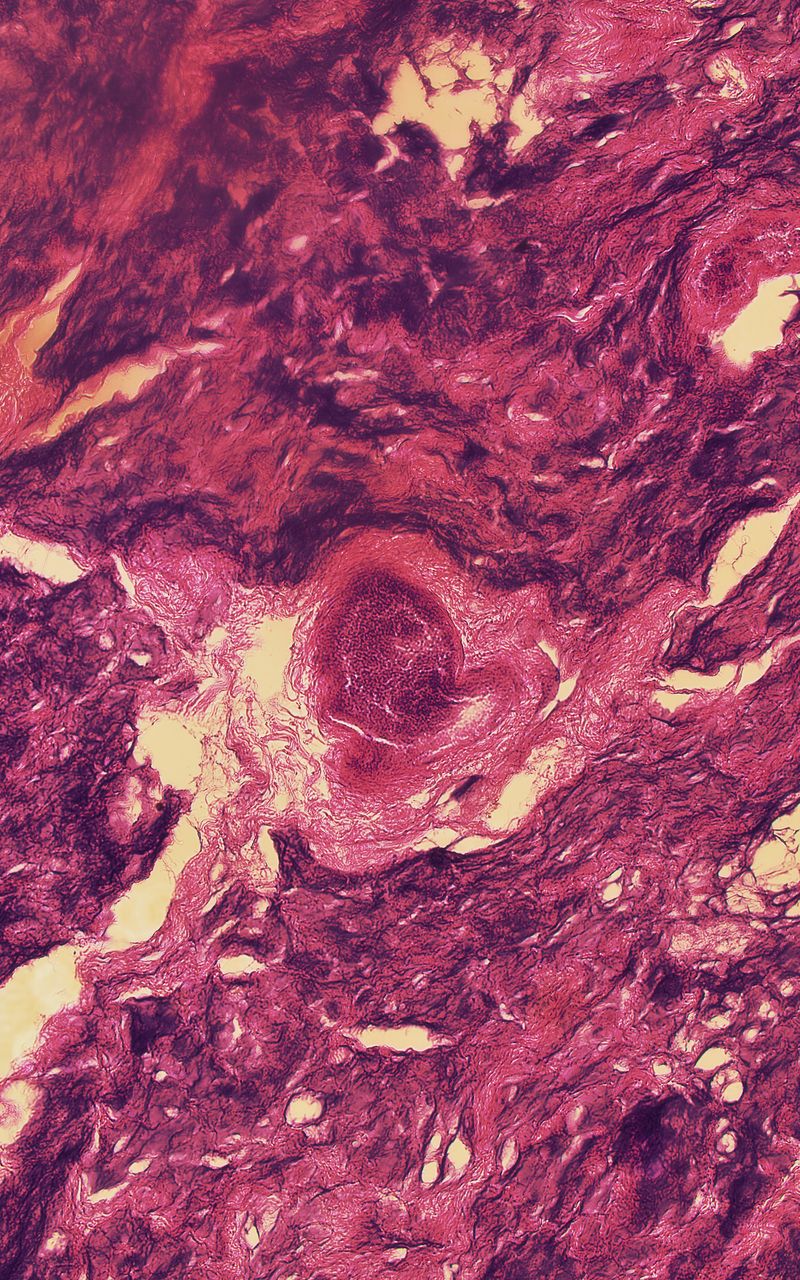

My work asks questions and challenges contemporary social and cultural attitudes towards the perception of death, the quality of life, reflections on the essence of humanity on philosophical and technological grounds. The story of our corporeality aims to begin a discourse about what has been tabooed or is socially marginalized:

medical bioengineering, technology in medical service, change in the perception of a dead body and the aspect of loss. Such a discourse could reveal the needs and solutions for the development of bioengineering in Poland. The increasingly appearing idea of transhumanism in this aspect considers dysfunctional elements of the human condition, such as disability, suffering, disease and ageing, to be undesirable, often still remaining only an idea but also a goal.